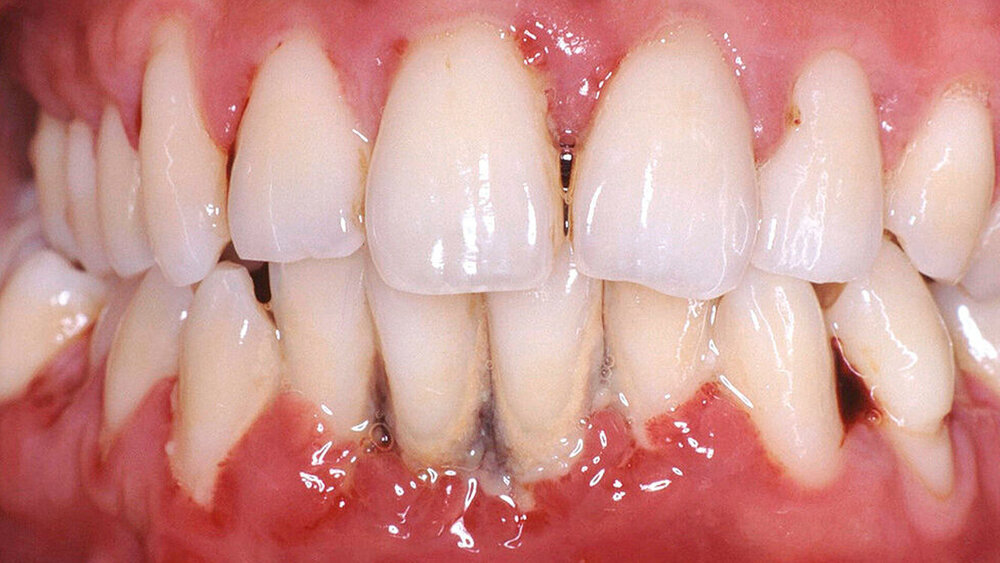

Mukogingivale Zustände

Die Bedeutung des Gingiva-Phänotyps – einschließlich der Gingivadicke und -breite – wird jetzt anerkannt und eine neue Klassifikation für gingivale Rezessionen ist eingeführt worden. Dabei werden klinische Parameter wie der gingivale Phänotyp, der interproximale Attachmentverlust und die Charakteristika der freiliegenden Wurzeloberfläche kombiniert.

Mukogingivale Zustände werden nach gingivalem Phänotyp, interproximalem Attachmentverlust und den Charakteristika der exponierten Wurzeloberfläche klassifiziert.